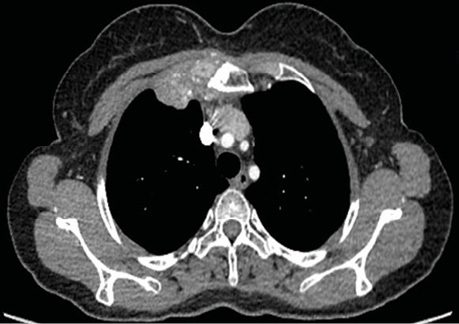

3D-реконструкція КТ до оперативного втручання підтвердила деструкцію ручки грудини пухлинним процесом (рис. 2).

Рис. 2. 3D-реконструкція КТ